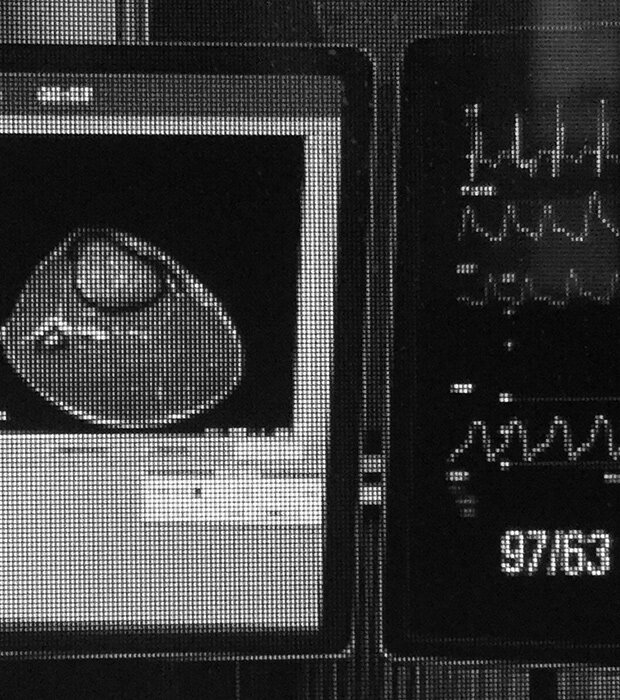

Информация с медицинскими данными пациента транслируется в режиме онлайн, специалист «на материке» изучает их, обсуждает с Дасаевым, помогает определить правильный диагноз и адекватное ситуации лечение.

Здесь установлены аппараты УЗИ, ЭКГ, оборудование для видеоконференций, специальные видеокамеры, корректно передающие цвета, — это важно, чтобы удаленный врач-консультант мог определить степень повреждения.

В 2004 году РЖД запустили поезда с телемедициной и переносные медицинские комплексы, которые можно за 20 минут развернуть на месте аварии. В таких поездах установлены аппараты УЗИ, маммографы, эндоскопы, рентген и лабораторный комплекс. Врачи могут развернуть дополнительную аппаратуру с помощью спутниковой связи проконсультировать пациента с врачами из ведущих клиник страны.

В декабре 2017 года Сбербанк, сервис Docdoc и сеть медицинских центров «Медскан» запустили совместный проект «Модуль здоровья». Это киоск для онлайн-консультаций с врачами, установленный в московском офисе Agile Home Сбербанка для сотрудников компании. В киоске находятся приборы, с помощью которых можно измерить давление, пульс и температуру, сделать кардиограмму и проконсультироваться с врачом по видеосвязи.